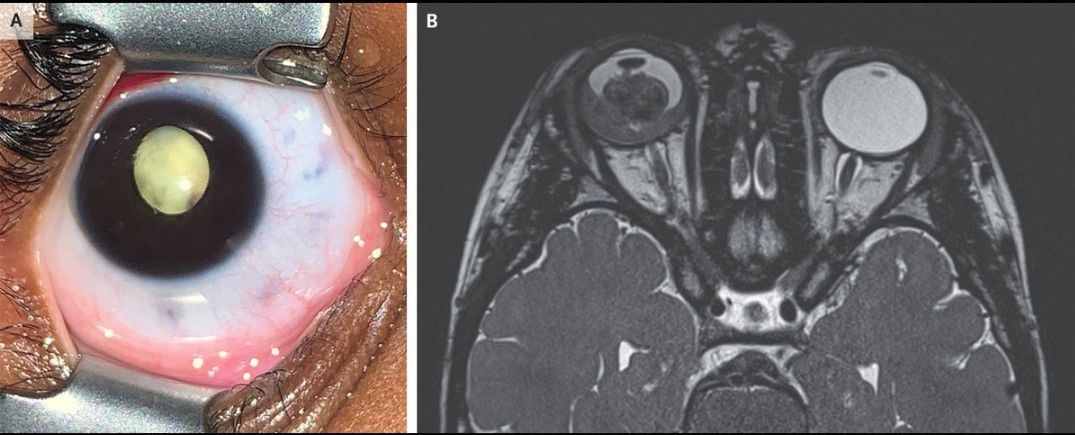

A 3-year-old girl was brought to the emergency department with a 2-month history of a white pupil and a 1-day history of redness and pain in the right eye. An eye examination performed while the patient was under anesthesia showed leukocoria (Panel A), as well as iris neovascularization and a white, nodular mass in the posterior chamber. The left eye was normal. B-scan ultrasonography showed tumor calcification and vitreous seeding in the affected eye. A diagnosis of retinoblastoma was made. Magnetic resonance imaging of the head showed retinal and choroidal invasion without extraocular extension (Panel B). Given the high-risk clinical features, the eye was enucleated the next day. Histopathological examination confirmed the diagnosis. Genetic testing did not show a germline mutation in the tumor suppressor gene RB1, and therefore the tumor was attributed to a somatic, nonheritable mutation. Leukocoria requires urgent evaluation by an ophthalmologist in order to quickly identify life-threatening causes. When detected early, retinoblastoma can be treated with focal therapy that can salvage vision and the eye. When diagnosis is delayed, however, the condition is often treated with enucleation and systemic chemotherapy to prevent life-threatening metastasis. After enucleation, the patient underwent six cycles of chemotherapy. There was no evidence of recurrent disease on subsequent examinations.